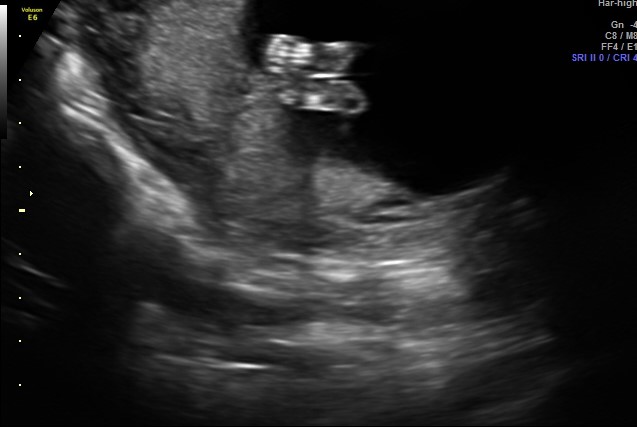

I was told a boy by this ultrasound photo, but i am having a hard time understanding the picture. Can someone help? I was sure I was having a girl, too, and this isn’t helping my confusion! https://uploads.tapatalk-cdn.com/201...d73731cca5.jpg